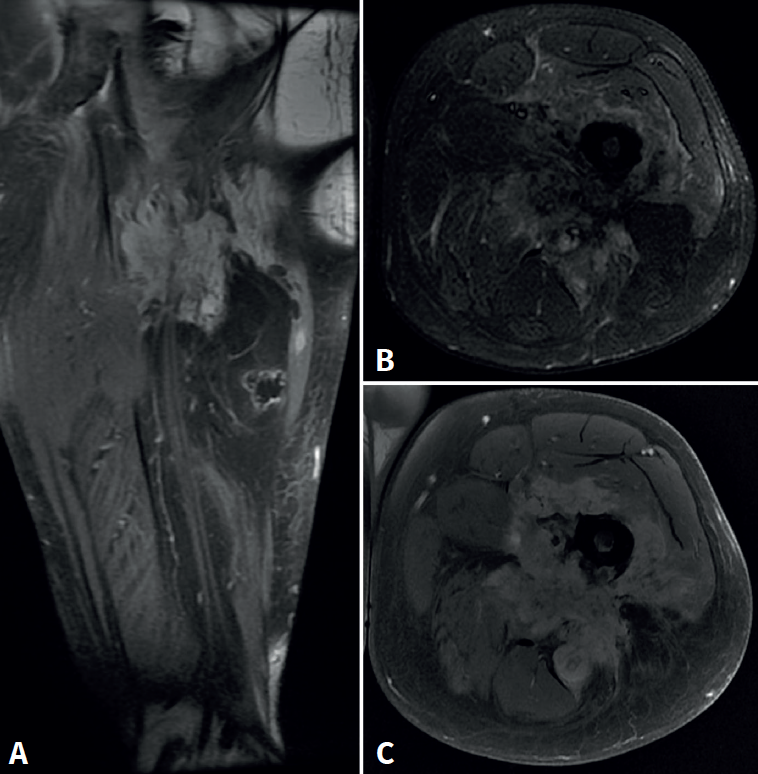

Cincuenta días tras el accidente se realizó fusión lumbar instrumentada L4-L5 con inserción de dispositivo intersomático por vía transforaminal derecha. En el segundo día postoperatorio presentó empeoramiento del dolor, objetivándose en la tomografía computarizada (Figura 2) malposición del tornillo L5 izquierdo que invadía el canal. Se reintervino a los 5 días corrigiendo el trayecto del tornillo. Sin embargo, persistió el dolor. La revaluación del caso, sumada a los hallazgos de EMG, motivó estudios complementarios de pierna y trayecto ciático (Figuras 3 y 4), detectándose una masa tumoral en el fémur izquierdo compatible con sarcoma fusocelular.